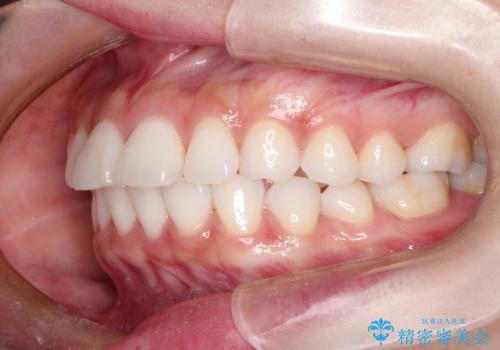

口が閉じにくい 口ゴボの抜歯矯正による改善

- 20代女性

- 口が閉じずらく、口元が出ていることを主訴に来院されました。

上下左右の歯を1本ずつ抜歯して、そのスペースを利用して口元を引っ込める計画としました。

口元を下げて口唇を閉じやすくする場合、抜歯矯正をお勧めさせていただくことが多いです。